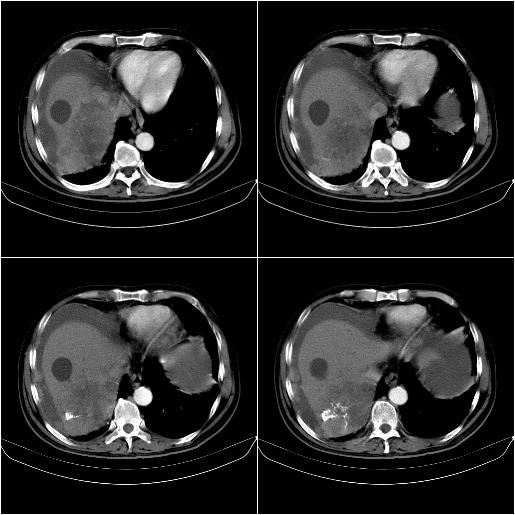

m,67y,肝癌9月,介入术后3月。现腹胀、纳差、腹泻。

1)肝癌介入治疗术后碘油沉积不良。2)门静脉瘤栓形成,腹膜广泛性转移。3)肝硬化,脾大,腹水。4)慢性胆囊炎。